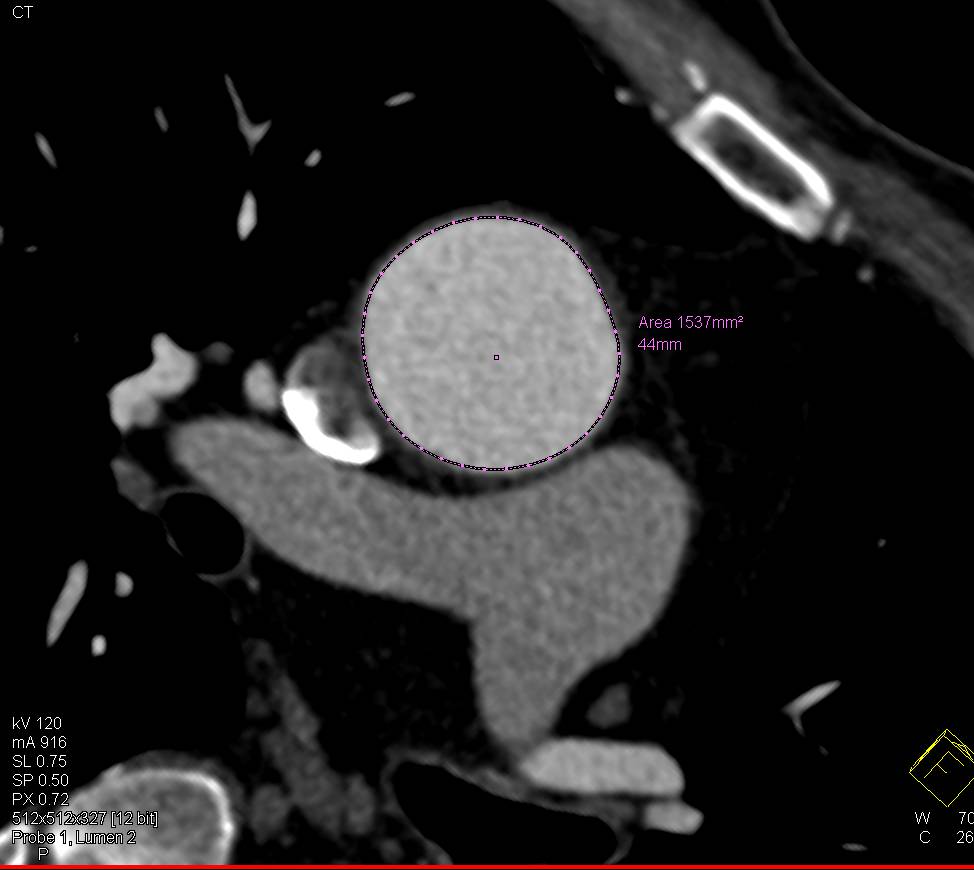

Patent Right Axillary Graft and Occluded Left Axillary Graft